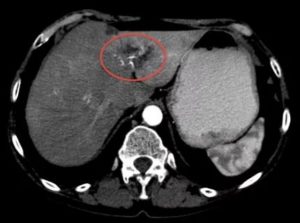

Гиподенсивные образования в печени возникают по различным причинам, это могут быть метастазы, кисты, опухоли, злокачественные новообразования. Если очаг превышает диаметр 4 сантиметра, показано проведение биопсии, сдача анализов крови на наличие маркеров гепатита для исключения онкологических заболеваний.

Что такое гиподенсивность, когда она проявляется

Под термином гиподенсивность необходимо понимать снижение плотности тканей печени. Каждая ткань человеческого организма отличается определенной плотностью, что видно на томографических и рентгеновских снимках. При патологиях печени структура органа становится неоднородного цвета, присутствуют затемненные участки. Обнаружение такого очага говорит о развитии заболевания.

Подобные изменения плотности могут быть симптомом любой патологии, от доброкачественных новообразований и до опасных для жизни злокачественных опухолей с метастазами. В ряде случаев гиподенсивные образования обусловлены наличием врожденных патологий.